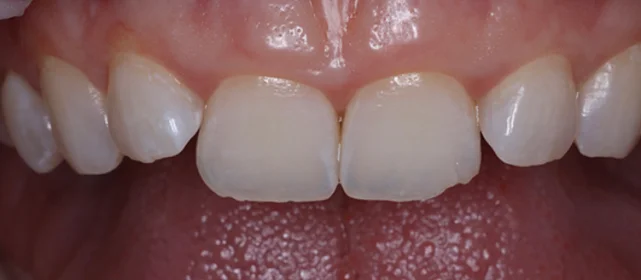

Зубы выровнены, смыкание нормализовано. Установлены несъёмные ретейнеры на обе челюсти, сняты сканы для ретенционных кап.

Решение: Поставили прозрачные элайнеры Click — начали с компактного набора из 20 кап. Основной комплект сделал основной объем работы, но для финальной доводки понадобился дополнительный набор из 10 кап. Итого 30 кап за 23 месяца. Результат — зубы на месте, смыкание в норме. Зафиксировали ретейнеры на обе челюсти, сняли сканы для ретенционных кап.

Мне поставили всего 20 кап, и я думала — за полтора года управлюсь. Вышло чуть дольше, потому что потребовался дозаказ. Но 10 дополнительных кап — это мелочь по сравнению с основным лечением. Зато результат довели до конца, а не остановились на «почти ровно».

Небольшой по объёму случай — 20 кап в основном наборе. Этого хватило для основного выравнивания, но финальная коррекция смыкания потребовала ещё 10 кап. Предпочитаю доработать, чем оставить компромиссный результат. 30 кап за 23 месяца — спокойный темп, без спешки.